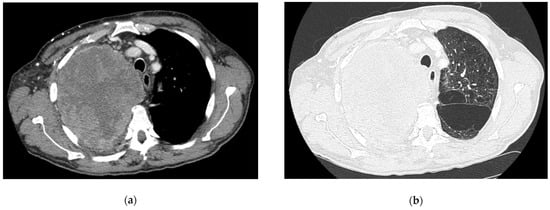

- Iguchi, T.; Hiraki, T.; Matsui, Y.; Fujiwara, H.; Sakurai, J.; Masaoka, Y.; Uka, M.; Tanaka, T.; Gobara, H.; Kanazawa, S. CT Fluoroscopy-Guided Core Needle Biopsy of Anterior Mediastinal Masses. Diagn. Interv. Imaging 2018, 99, 91–97. [Google Scholar] [CrossRef] [PubMed]

- Drumm, O.; Joyce, E.A.; de Blacam, C.; Gleeson, T.; Kavanagh, J.; McCarthy, E.; McDermott, R.; Beddy, P. CT-Guided Lung Biopsy: Effect of Biopsy-Side Down Position on Pneumothorax and Chest Tube Placement. Radiology 2019, 292, 190–196. [Google Scholar] [CrossRef]

- Petranovic, M.; Gilman, M.D.; Muniappan, A.; Hasserjian, R.P.; Digumarthy, S.R.; Muse, V.V.; Sharma, A.; Shepard, J.-A.O.; Wu, C.C. Diagnostic Yield of CT-Guided Percutaneous Transthoracic Needle Biopsy for Diagnosis of Anterior Mediastinal Masses. AJR Am. J. Roentgenol. 2015, 205, 774–779. [Google Scholar] [CrossRef]

- Skretting, I.K.; Ruud, E.A.; Ashraf, H. Diagnostic Yield, Complications, Pathology and Anatomical Features in CT-Guided Percutaneous Needle Biopsy of Mediastinal Tumours. PLoS ONE 2022, 17, e0277200. [Google Scholar] [CrossRef]